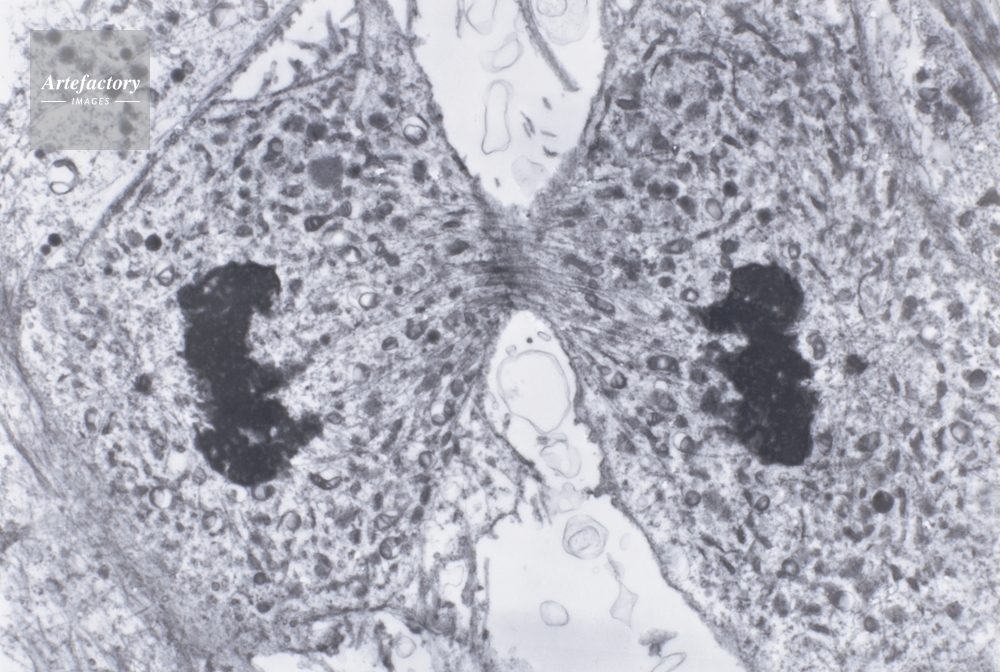

| 作品タイトル | ネズミ体細胞核分裂・終期 | モデルリリース | なし | |

| キャプション | 電顕倍率約2400倍 | 制限事項 | ||